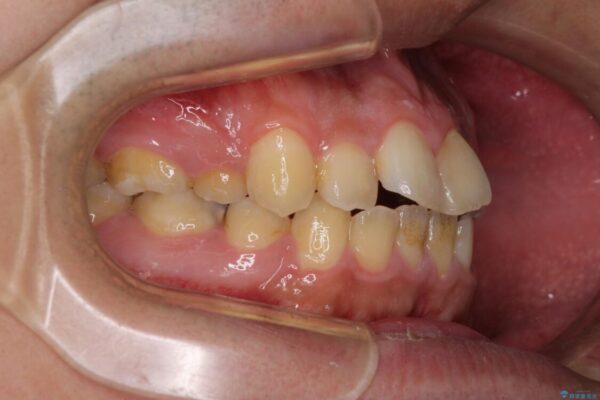

治療前

• 後戻りでデコボコの前歯 インビザライン矯正治療 治療前画像